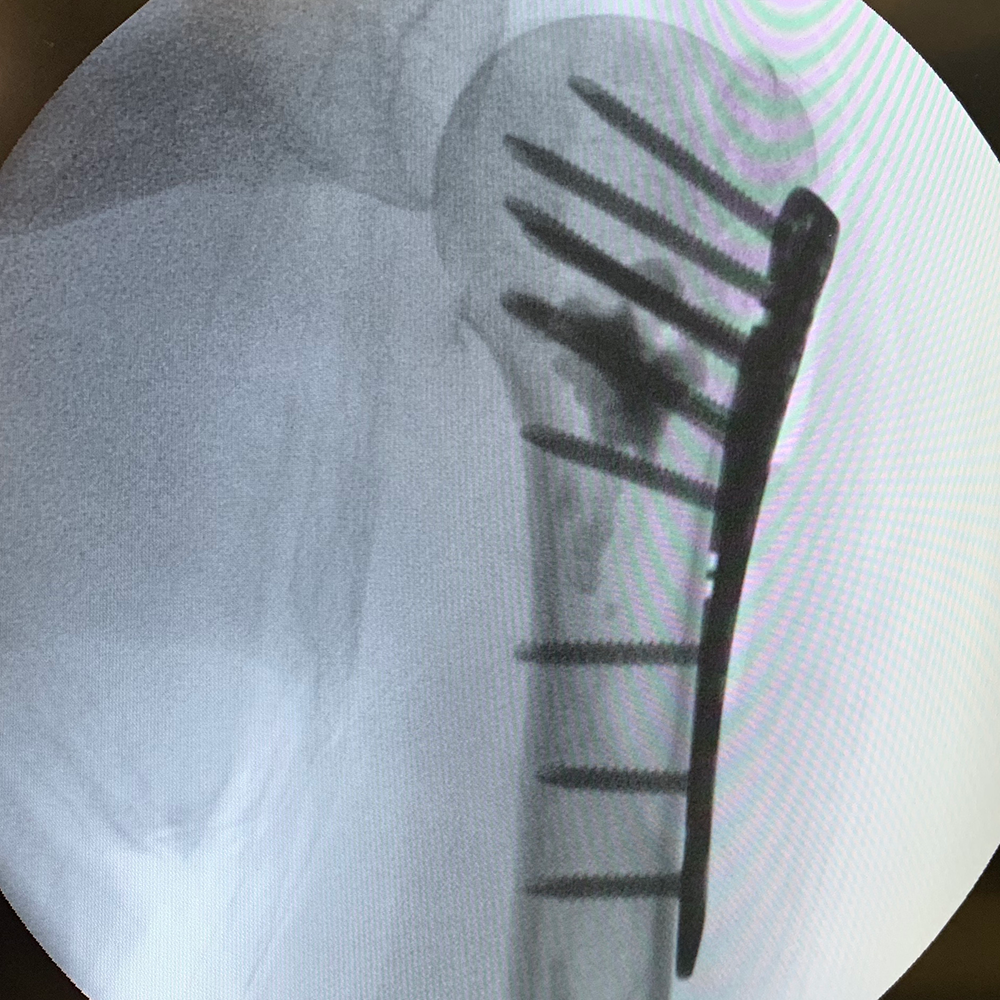

PLATING SYSTEM

- 40° Polyaxial locking

- Strong & consistent locking mechanism

- Low profile construct

- Titanium low-profile construct

- Locking caps allow all screws to compress the plate to bone before locking

- Locking caps improve fatigue properties and prevent screw back out

- Precise screw placement independent of plate position

- A single screw can be used to lag and then be locked into place without changing screw or disrupting reduction

- Polyaxial drill guides allows for provisional K-wire fixation

- The low profile design allows for optimal contour of the plate proximally